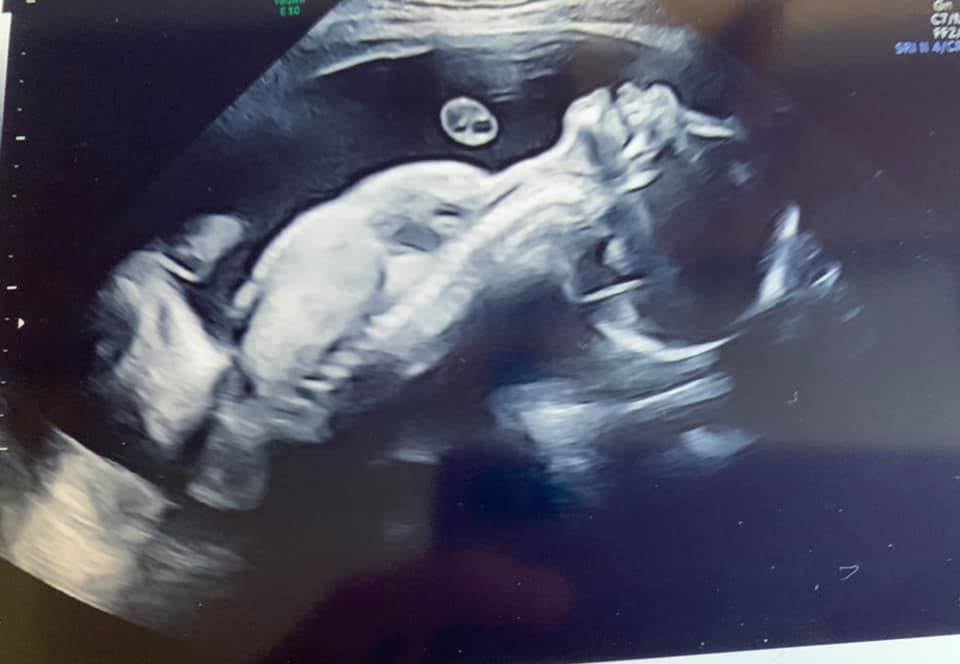

and a final appointment with my paediatrician… a new choice is I’ve now requested intubation at birth if needed. Something I was originally going to avoid on the basis of her diagnosis but because of some positives in scans and because of my endless research into Trisomy 18 I now believe she has a reasonable chance of life (how long for is unknown) and I want to ensure she is fully assessed and not judged simply on the basis of her diagnosis. Martin McCaffrey also told me if she makes it past 1 month we have a 40% chance of survival past her 1st birthday.. I realise that must sound horrific to you all but I have gone through this pregnancy believing she only had a 5-10% chance of this so I’m clinging to hope.. it is all I have at this point.So to Ambers scan.. my fluid levels has gone up high this week … not great but hopefully will cause no problems. Her heartbeat

is strong! Cord flow good and her weight… has gone up!! My baby girl is now estimated at 5lbs3oz which is INCREDIBLE for a Trisomy 18 baby!! Just over a whole lb more than last week! (that’s bigger than mum said said my sister Wendy was!! ![]()

) And.. I don’t know how much to read into this but Ambers hand was OPEN! To explain the excitement of this you need to understand that Trisomy 18 babies usually have clenched fists as Amber has had at all her scans so far.. this is a signifier of neurological/brain issues … so for her hand to be open is maybe a good sign?? I’ll be speaking to my paediatrician tomorrow and asking her opinion

Photos from today

Ambers tiny open hand and face and also a gorgeous photo of the wee jacket and bonnet my mum has knitted for Amber.. ready to pack in my hospital bag ![]()